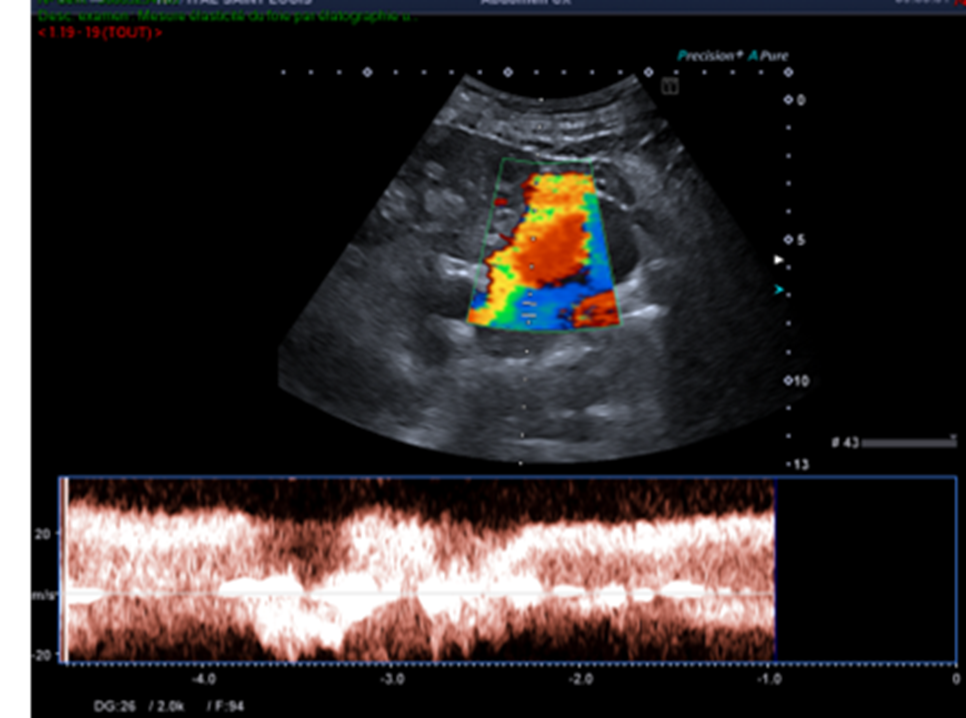

Celui qui aura balayé entièrement l’organe et son environnement, et qui aura complété son examen par le doppler couleur répondra différemment.

Ces nouvelles coupes (faisant apparaitre la rate, le doppler couleur et le doppler pulsé), montrent alors non pas un kyste rénal mais des volumineuses veines péri spléniques correspondant à des voies de dérivations spléno-rénales témoignant d’une hypertension portale probablement liée à la cirrhose sous-jacente.